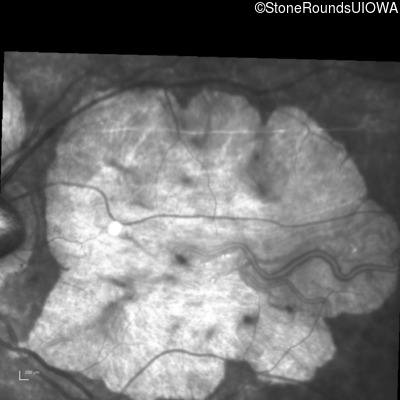

Infrared Fundus Photograph - Right - 10/160 sc

Exemplar